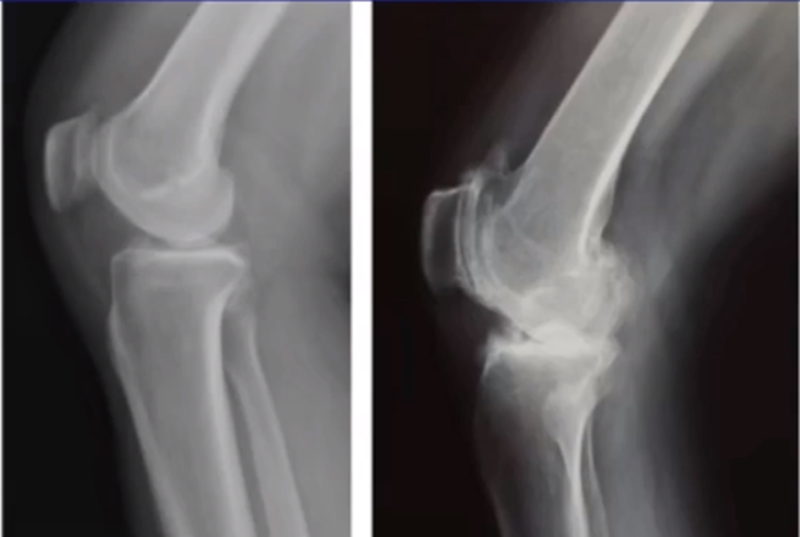

牛津单髁影像学判断的标准为通过负重正位片来判断内侧间室关节软骨的磨损程度。内侧间室关节间隙变窄,股骨内侧髁与内侧胫骨平台成“骨磨骨”状态,说明内侧间室软骨磨损丢失。如果没有在正位片观察到“骨磨骨”,则需要通过内翻应力位片或rosenberg位检查,找到骨磨骨的证据。如果以上均没有显示骨磨骨,需考虑关节镜检查,只有在达到“骨磨骨”的情况下才考虑行UKA。

AMOA查体与X线特点,站立位屈曲内翻

AMOA的X线正位的表现